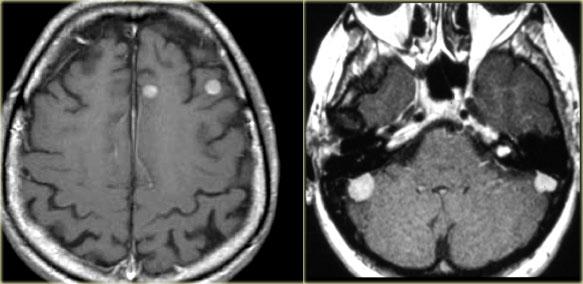

TRÁI: Di căn não. PHẢI: Nhiều u màng não và u thần kinh bao ở bệnh nhân U xơ thần kinh type II (Neurofibromatosis II)

Bệnh đa ổ

Nhiều khối u trong não thường gợi ý bệnh di căn (hình minh họa).

Các u não nguyên phát thường gặp ở một vùng duy nhất, nhưng một số u não như u lympho, u nguyên bào đa hình đa trung tâm (multicentric GBM) và u thần kinh đệm lan tỏa não (gliomatosis cerebri) có thể đa ổ.

Một số khối u có thể đa ổ do di căn gieo rắc: điều này có thể xảy ra trong u nguyên tủy bào (PNET-MB), u màng nội tủy (ependymoma), u nguyên bào đa hình (GBM) và u tế bào ít nhánh (oligodendroglioma).

U màng não và u thần kinh bao có thể xuất hiện nhiều ổ, đặc biệt trong bệnh u xơ thần kinh type II.